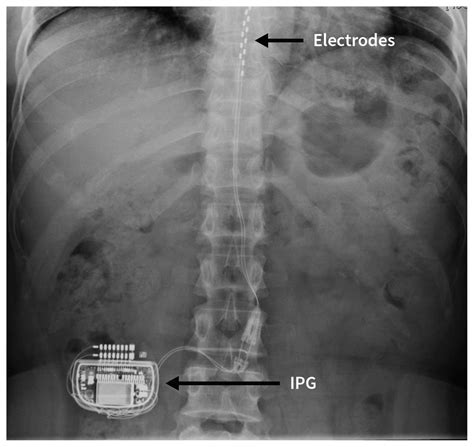

A spinal cord stimulator (SCS) is a device implanted under the skin that sends a mild electric current to your spinal cord. The surgery is essentially a two-part process designed to see how your body responds to the electrical pulses. This procedure is generally recommended for patients suffering from conditions such as failed back surgery syndrome, complex regional pain syndrome (CRPS), or peripheral neuropathy.

• The Permanent Implantation: If the trial is successful—meaning you experience at least 50% reduction in pain—a follow-up surgery is scheduled to implant the internal pulse generator (IPG) under the skin, usually in the buttock or abdominal area.

On the day of the procedure, you will be sedated, and the surgeon will use fluoroscopy (a real-time X-ray) to guide the leads into the precise location along the spinal column. Most patients are able to go home the same day or the following morning, depending on the complexity of the implantation.